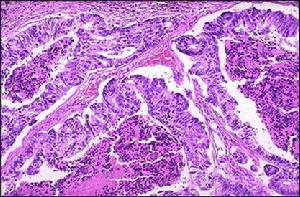

顯微鏡下:腫瘤成分有纖維組織、粘液組織和軟骨組織,多少不一。早期粘液組織為主要成分,有的部位細胞疏鬆或緻密,呈不規則分葉狀。小葉中瘤細胞為梭形或緻密,呈不規則分葉狀。小葉中瘤細胞為梭形或星形,胞核染色深。瘤細胞之間為粘液,但染色陰性。小葉邊緣瘤細胞十分密集,血管豐富,胞核大,可有兩核、多核。可有陳舊性出血。粘液可纖維化、或演變為軟骨樣組織。在大片纖維組織中,可見大小不一的軟骨島。